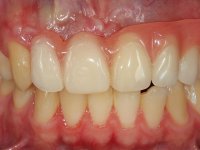

Paciente do sexo masculino, com 22 anos de idade e não fumador. Apresentou-se na consulta 6 meses após um acidente de viação em que perdeu os dentes 21, 22, 23 e 24. Os dentes 12 e 11 apresentavam mobilidade grau 3 apresentando-se também com extracção indicada. A arquitectura gengival da zona desdentada apresentava-se retraída e planificada.

O paciente foi observado conjuntamente e a dúvida que surgiu de imediato foi se seria possível com a regeneração óssea a efectuar poder ser reabilitada naturalmente a zona das papilas interdentárias. Nesse sentido foi feito um enceramento de diagnóstico que contemplaria as duas hipóteses, utilizando ou não a cerâmica gengival. A confecção desse enceramento foi fundamental para expor ao paciente a dificuldade da reabilitação. O wax-up deu origem a um mock-up que foi aprovado pelo paciente e que simultaneamente serviu de guia imagiológica. O caso foi planificado cirurgicamente e realizada uma guia cirúrgica com que foram colocados os implantes. Após 10 semanas foi feita a 1ª impressão para confecção da ponte provisória. Foram criados os primeiros perfis de emergência na gengiva artificial e foi digitalizado o modelo. Por processo de CAD-CAM foi confeccionada uma ponte provisória aparafusada baseada no enceramento de diagnóstico. A ponte trabalhou durante 8 semanas os tecidos moles que foram fielmente copiados numa impressão com técnica de moldeira aberta. Os transferes foram individualizados com resina composta para copiarem fielmente os perfis de emergência criados pela ponte provisória. Confeccionado o modelo de trabalho definitivo, foi realizada uma infra-estrutura em zircónio seguindo a orientação do enceramento de diagnóstico. O assentamento da infra-estrutura foi testado em boca e simultaneamente foi novamente impressionados os tecidos moles com um silicone fluido. Nessa consulta foi feito o levantamento da cor. Os dentes 13 e 23 apresentavam uma saturação anormalmente forte que resolvemos não valorizar, optando por privilegiar a relação com o sector antero-inferior. Foi realizada uma nova gengiva artificial com a impressão que acompanhou a impressão de arrasto com a infra-estrutura. Após a colocação da cerâmica na infra-estrutura foram coladas as meso-estruturas. O trabalho final foi aparafusado lentamente permitindo a adaptação dos tecidos moles.